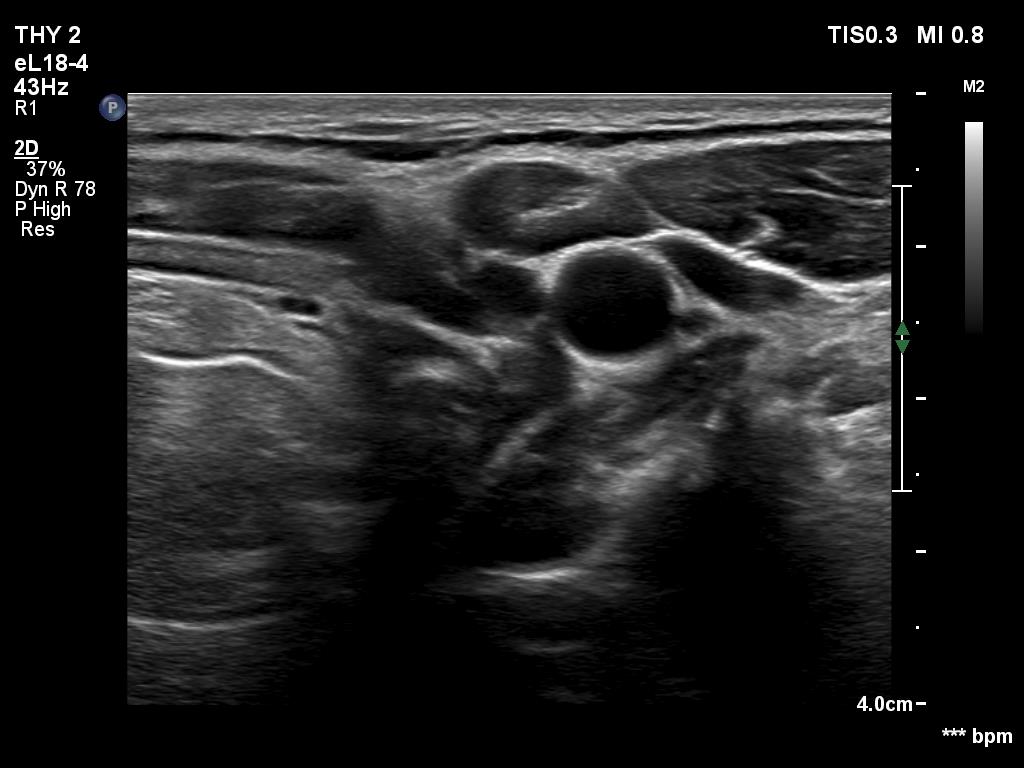

There was a hypoechoic mass with a regular hilum in the left submandibular area. The echo pattern was identical to the neighboring muscle fiber.

The differentiation of a lymph node from a discrete thickening of a muscle fiber can be challenging. If the node in this case would be non-palpable then it would be almost impossible to make this distinction. The echo patterns are identical and hilum-like adipose tissue is a common finding in muscle fibers. The only important ultrasound feature is the presence of vascularity according to the hilum. This was not demonstrated on color Doppler mode but was on microflow imaging.